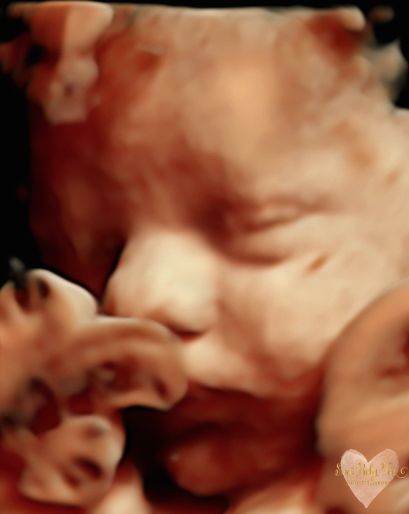

3D/4D/5D Ultrasound Gallery

Take a peek at our Photo Gallery. All of our 2D, 3D, 4D, HD elective ultrasound images are truly ours. They come directly off our machine from our highly trained staff. We can start getting great 3D/4D images as early as 10 weeks!